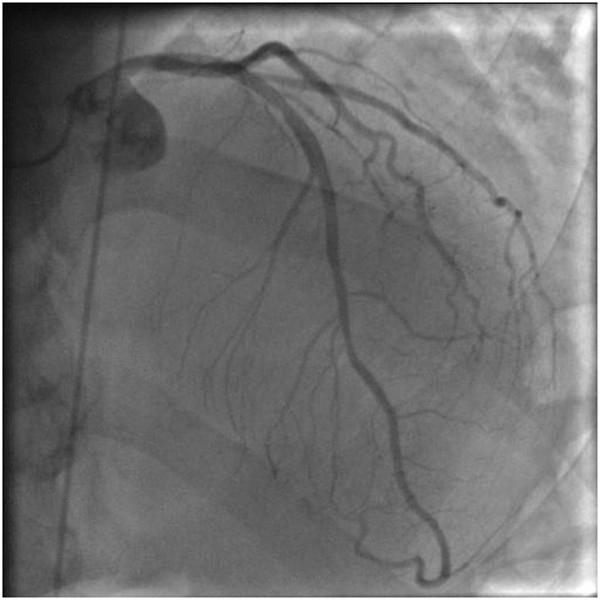

Radiation recall reaction causing cardiotoxicity.

Radiation recall phenomenon is a tissue reaction that develops within a previously irradiated area, precipitated by the subsequent administration of certain chemotherapeutic agents. It commonly affects the skin, but can also involve internal organs with functional consequences. To our best knowledge, this phenomenon has never been reported as a complication on the heart and should be consider as a potential cause of cardiotoxicity.